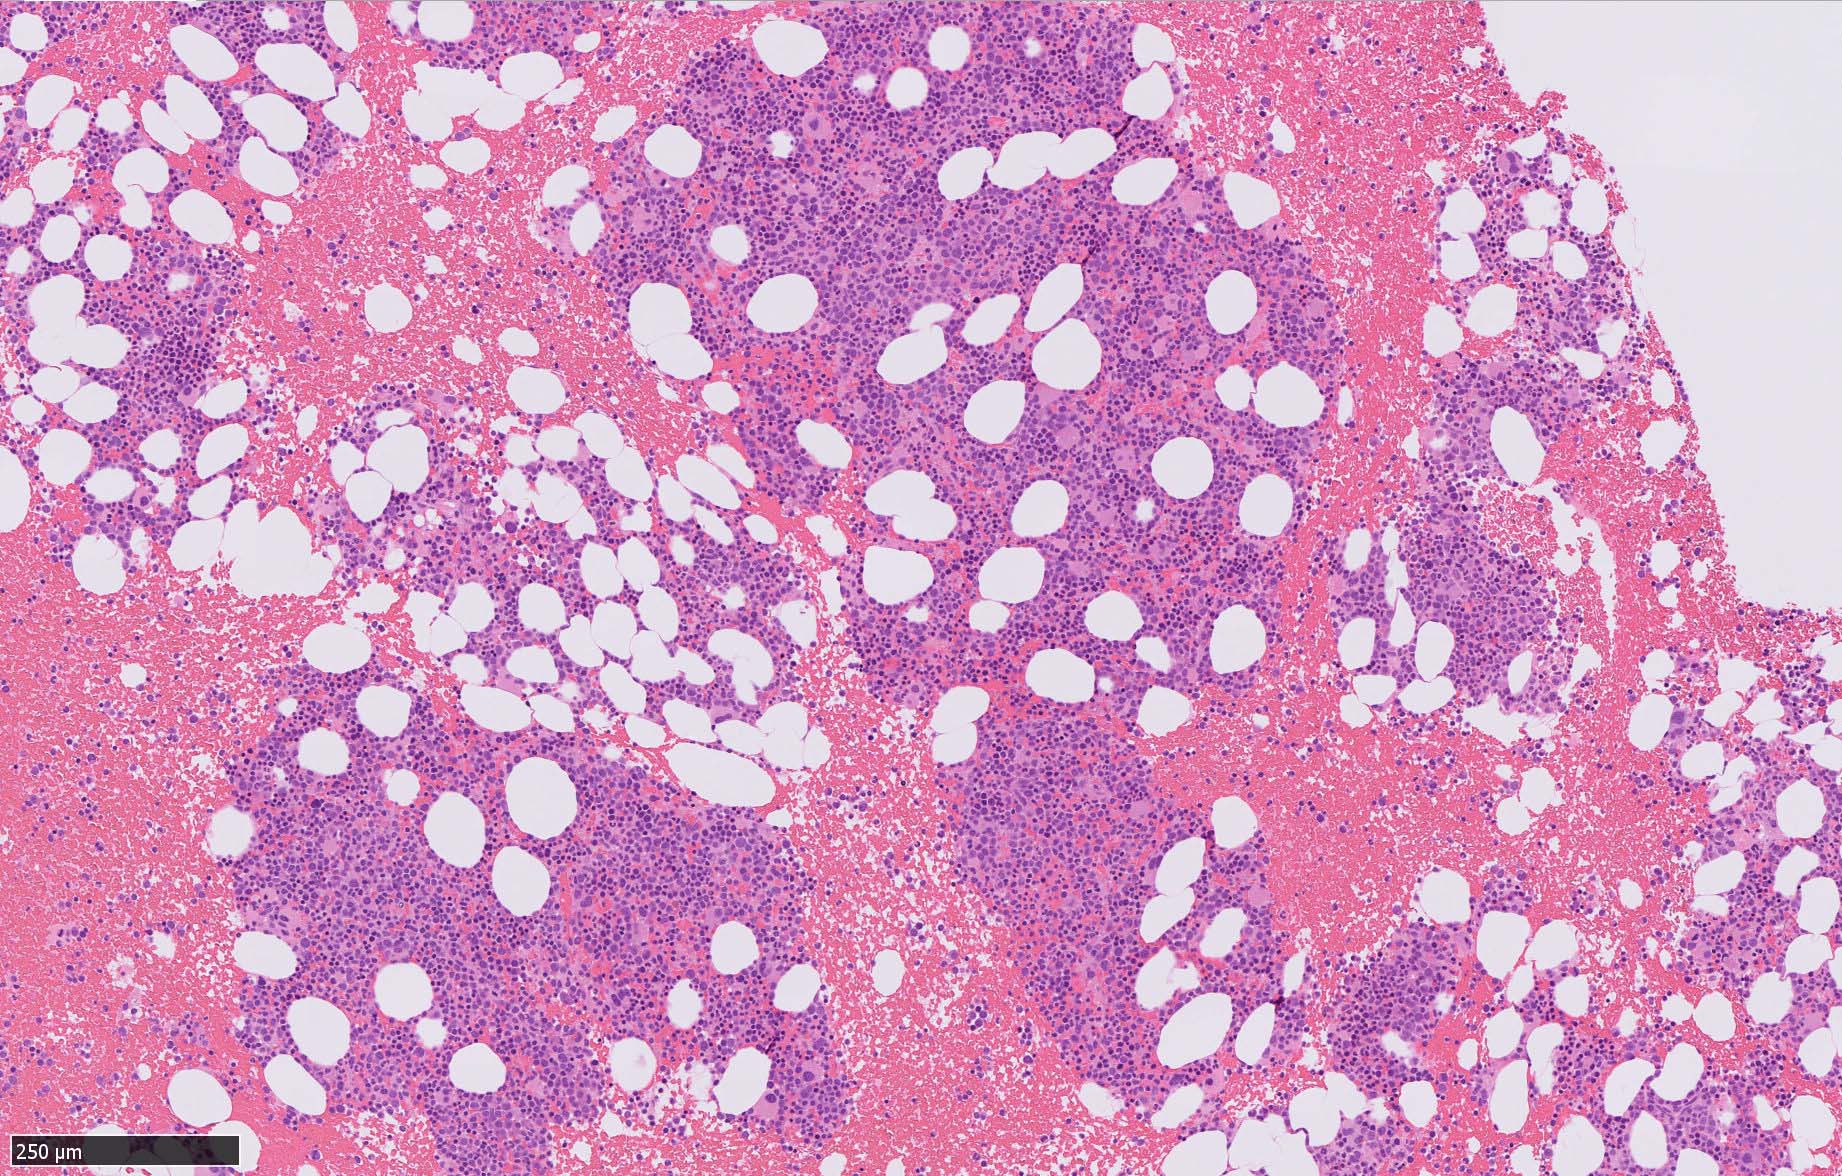

骨髄病理所見

HEでは腫瘍細胞の同定が難しい. 本症例は ASD-Giemsa染色を見ても, 腫瘍胞巣はよくわからなかった. 皮膚が先に診断がつき, 次いでBone marrowだったため, 免疫染色にすすめたが, Bone marrowが先だと診断に困ったかもしれない.

BPDCN骨髄病変の病理

症例骨髄に認められた異形成造血所見

Mgkは低分葉, 円形単核の細胞が多く, 分離円形核のMgkもみられた. 赤芽球はproerythroblstsのみの小集簇や孤在性出現あり. 成熟赤芽球が乏しい. 顆粒球系細胞も分葉好中球への分化像が少ない.

免疫染色では, HbFを発現する赤芽球の集簇巣が散見しているほか, p53陽性細胞が軽度に増加している. CD34陽性細胞増加はなし.CD42b染色でmicroMgkはみられなかった. 異形成造血が強く疑われる.